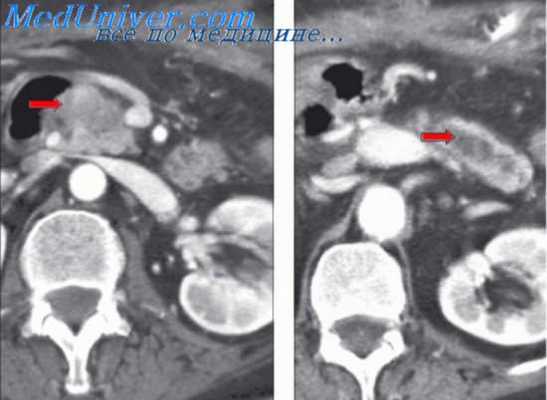

- Развитие предпеченочной портальной гипертензии (3-4 %) связано с нарушением кровотока в портальной и селезеночных венах вследствие их тромбоза, стеноза, сдавления и т. д.

- В структуре внутрипеченочной портальной гипертензии (85-90 %) различают пресинусоидальный, синусоидальный и постсинусоидальный блок. В первом случае препятствие на пути внутрипеченочного кровотока возникает перед капиллярами-синусоидами (встречается при саркоидозе, шистосомозе, альвеококкозе, циррозе, поликистозе, опухолях, узелковой трансформации печени); во втором – в самих печеночных синусоидах (причины - опухоли, гепатиты, цирроз печени); в третьем – за пределами печеночных синусоидов (развивается при алкогольной болезни печени, фиброзе, циррозе, веноокклюзионной болезни печени).